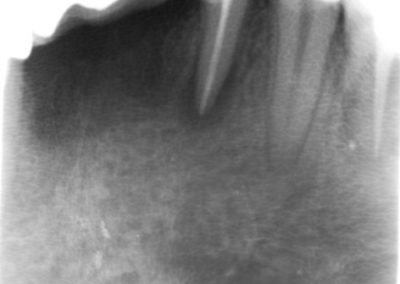

During the consultation, the dentist will first listen to your concerns and carry out appropriate tests to identify the right tooth that is causing pain. As a part of the diagnosis, your dentist will carry out various clinical tests to identify the right tooth and will take some radiographs which can aid in the diagnosis.

An access cavity is placed on the surface where the patient bites, to reach the root canals of the tooth. Once all the canals are identified, small files are used to remove the infected pulp.

Files of different sizes are used to eliminate bacteria and infection and to shape the canals. The canals are disinfected thoroughly with irrigants and later the canals will be sealed in 3 dimensions with a special medicament called gutta-percha to prevent reinfection of the tooth and the access cavity will be sealed with a temporary filling.